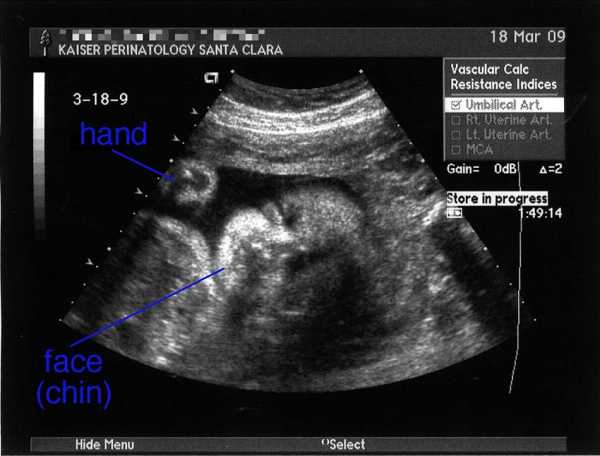

УЗИ на 31 неделе беременности

На 31 неделе беременности с помощью УЗИ можно будет определить положение ребенка, его предположительный рост и вес во время родов. Именно сейчас можно понять, будут ли роды проходить естественным путем или с помощью кесарева сечения. Однако, решение может измениться по ходу беременности: никто не может дать 100%-ных гарантий правильности развития плода.

Очень увлекательно наблюдать за действиями младенца в утробе: он уже не маленькое пятно, похожее на персик, а человек, который что-то умеет и знает. Можно увидеть, как он сосет пальчик, играет с пуповиной. Если малыш сосет палец на правой руке, то, скорее всего, родится правша, если левой – то левша.

На 31 неделе беременности можно с вероятностью 99% говорить о половой принадлежности ребенка, если, конечно, родители не хотят сделать себе сюрприз. На самом деле совсем не важно, кто это будет, девочка или мальчик, главное, чтобы малыш родился здоровым.

Важность УЗИ неоспорима. Иногда будущие матери отказываются от исследования, аргументируя это тем, что раньше женщины рожали и без него. Но сейчас наука идет вперед, с помощью этих недолгих манипуляций можно предсказать болезни или возможные нарушения в организме малыша. Отказываясь от врачебной помощи, будущая мать рискует здоровьем и жизнью своего ребенка.

Фото УЗИ на 31 неделе беременности